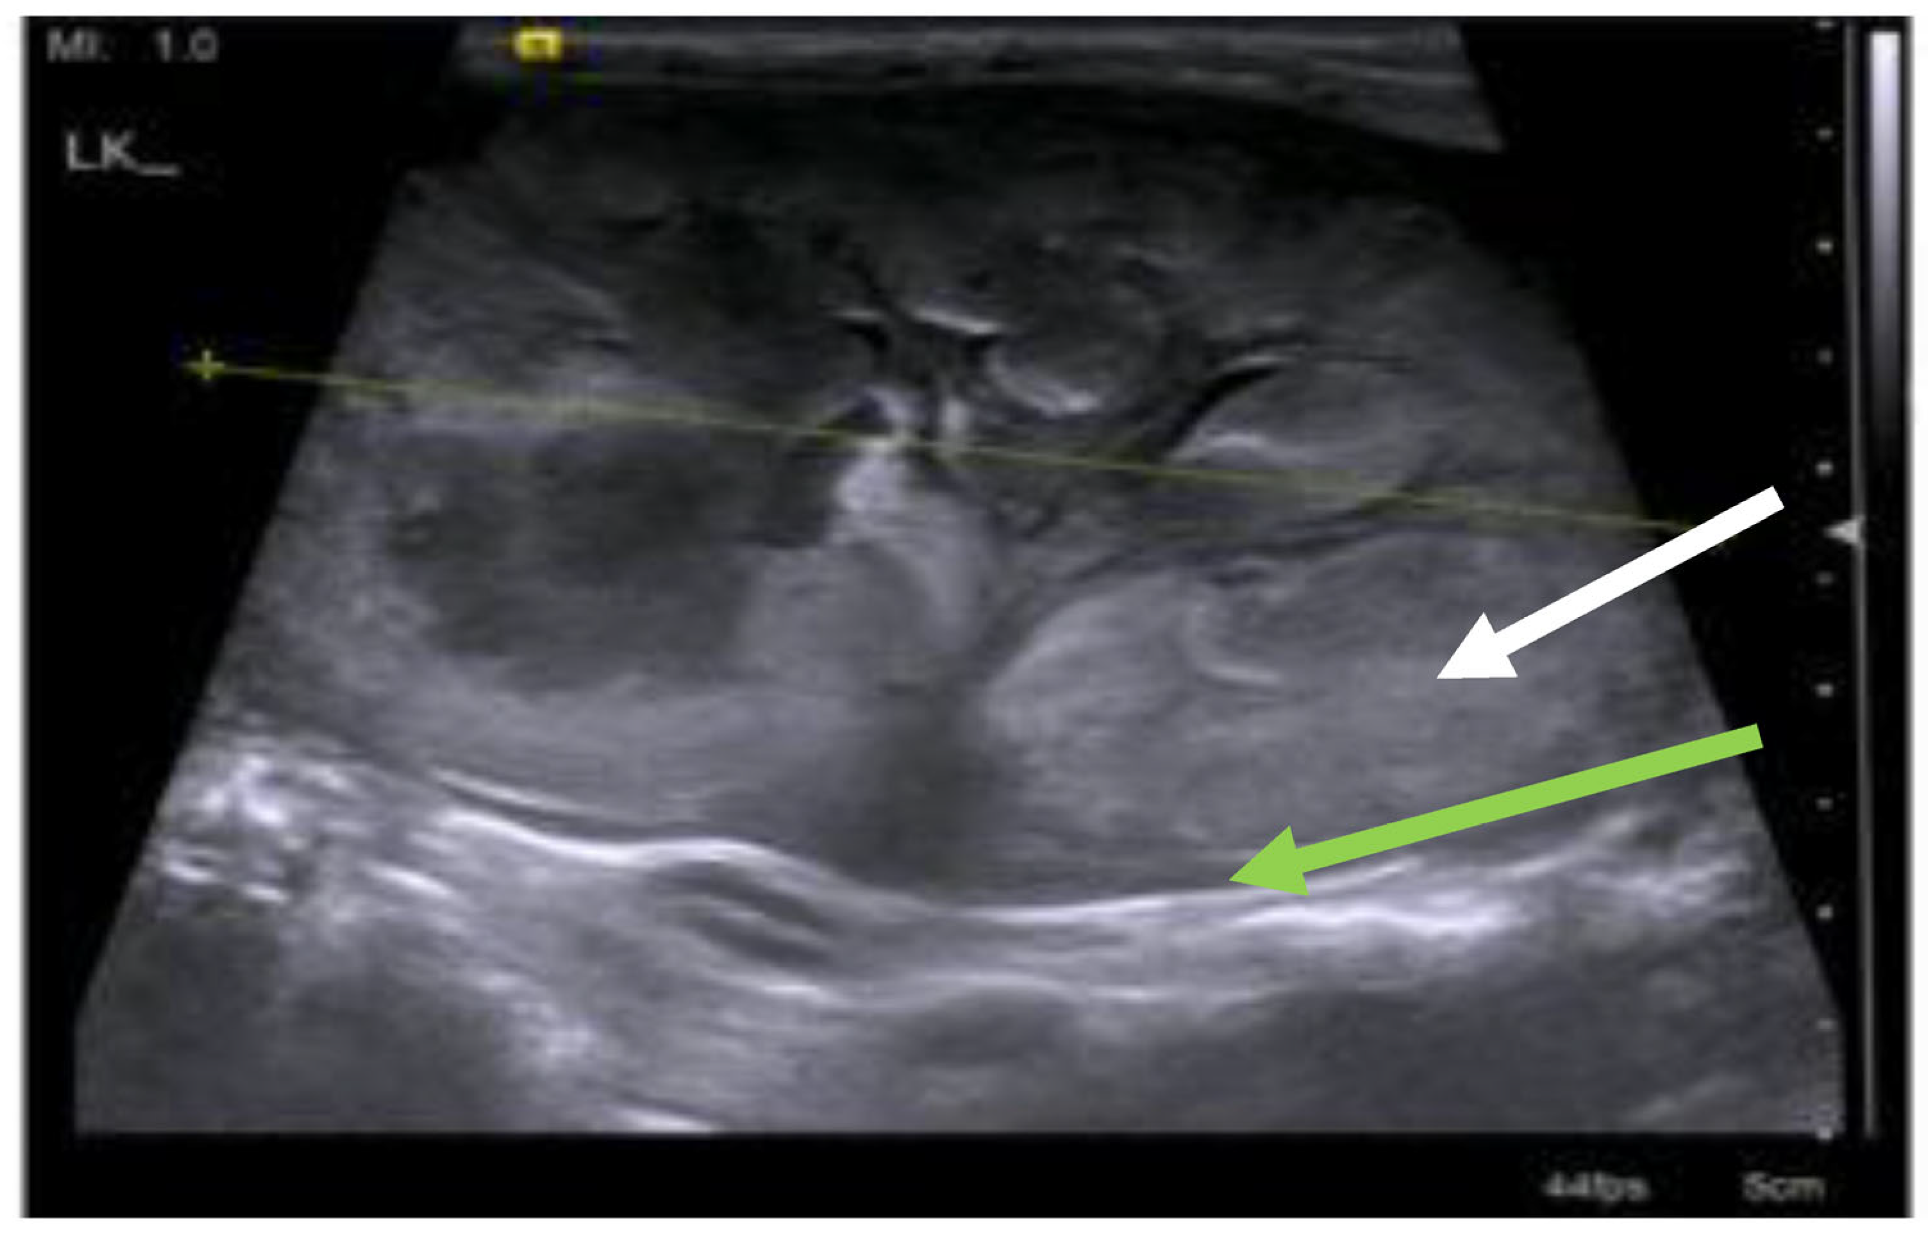

7.4. Diagnostic Imaging in FIP

7.4.1. Routine Imaging: Ultrasonographic and Radiographic Findings

7.4.2. Advanced Imaging of the CNS: MRI and CT